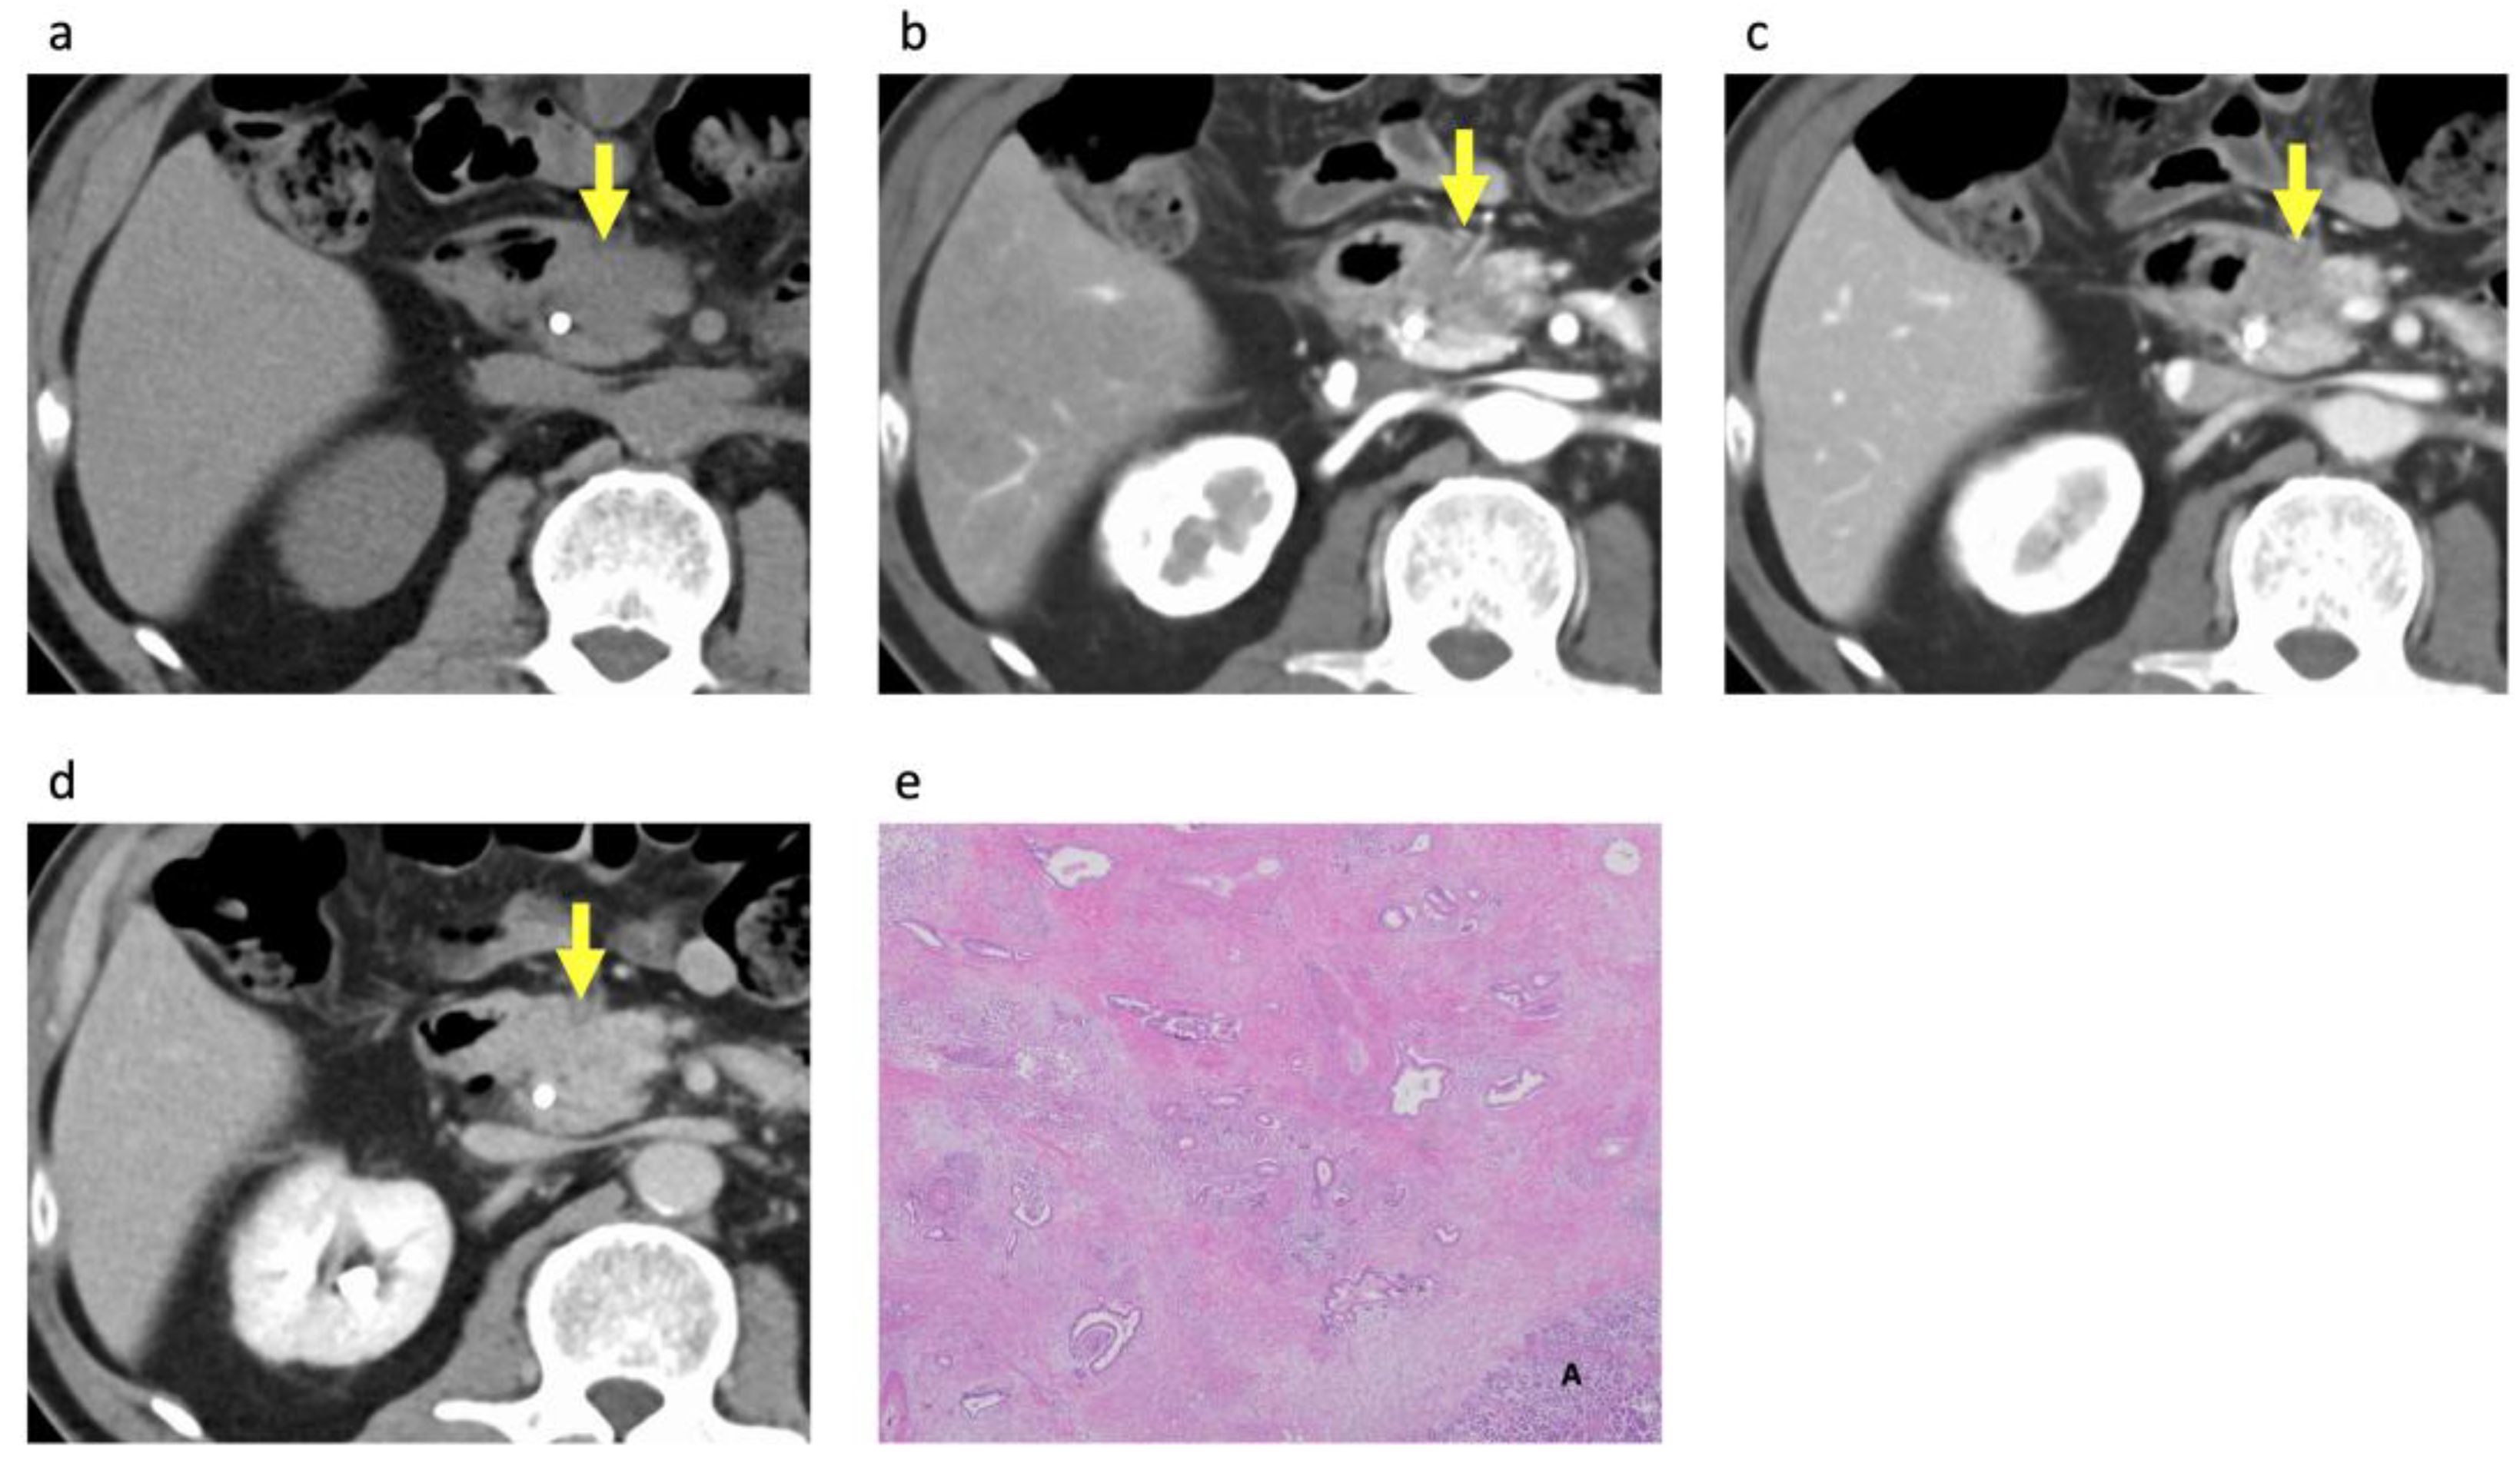

3.2. CECT Imaging Findings

3.3. Histopathological Analysis of the PDACs According to Rim Enhancement